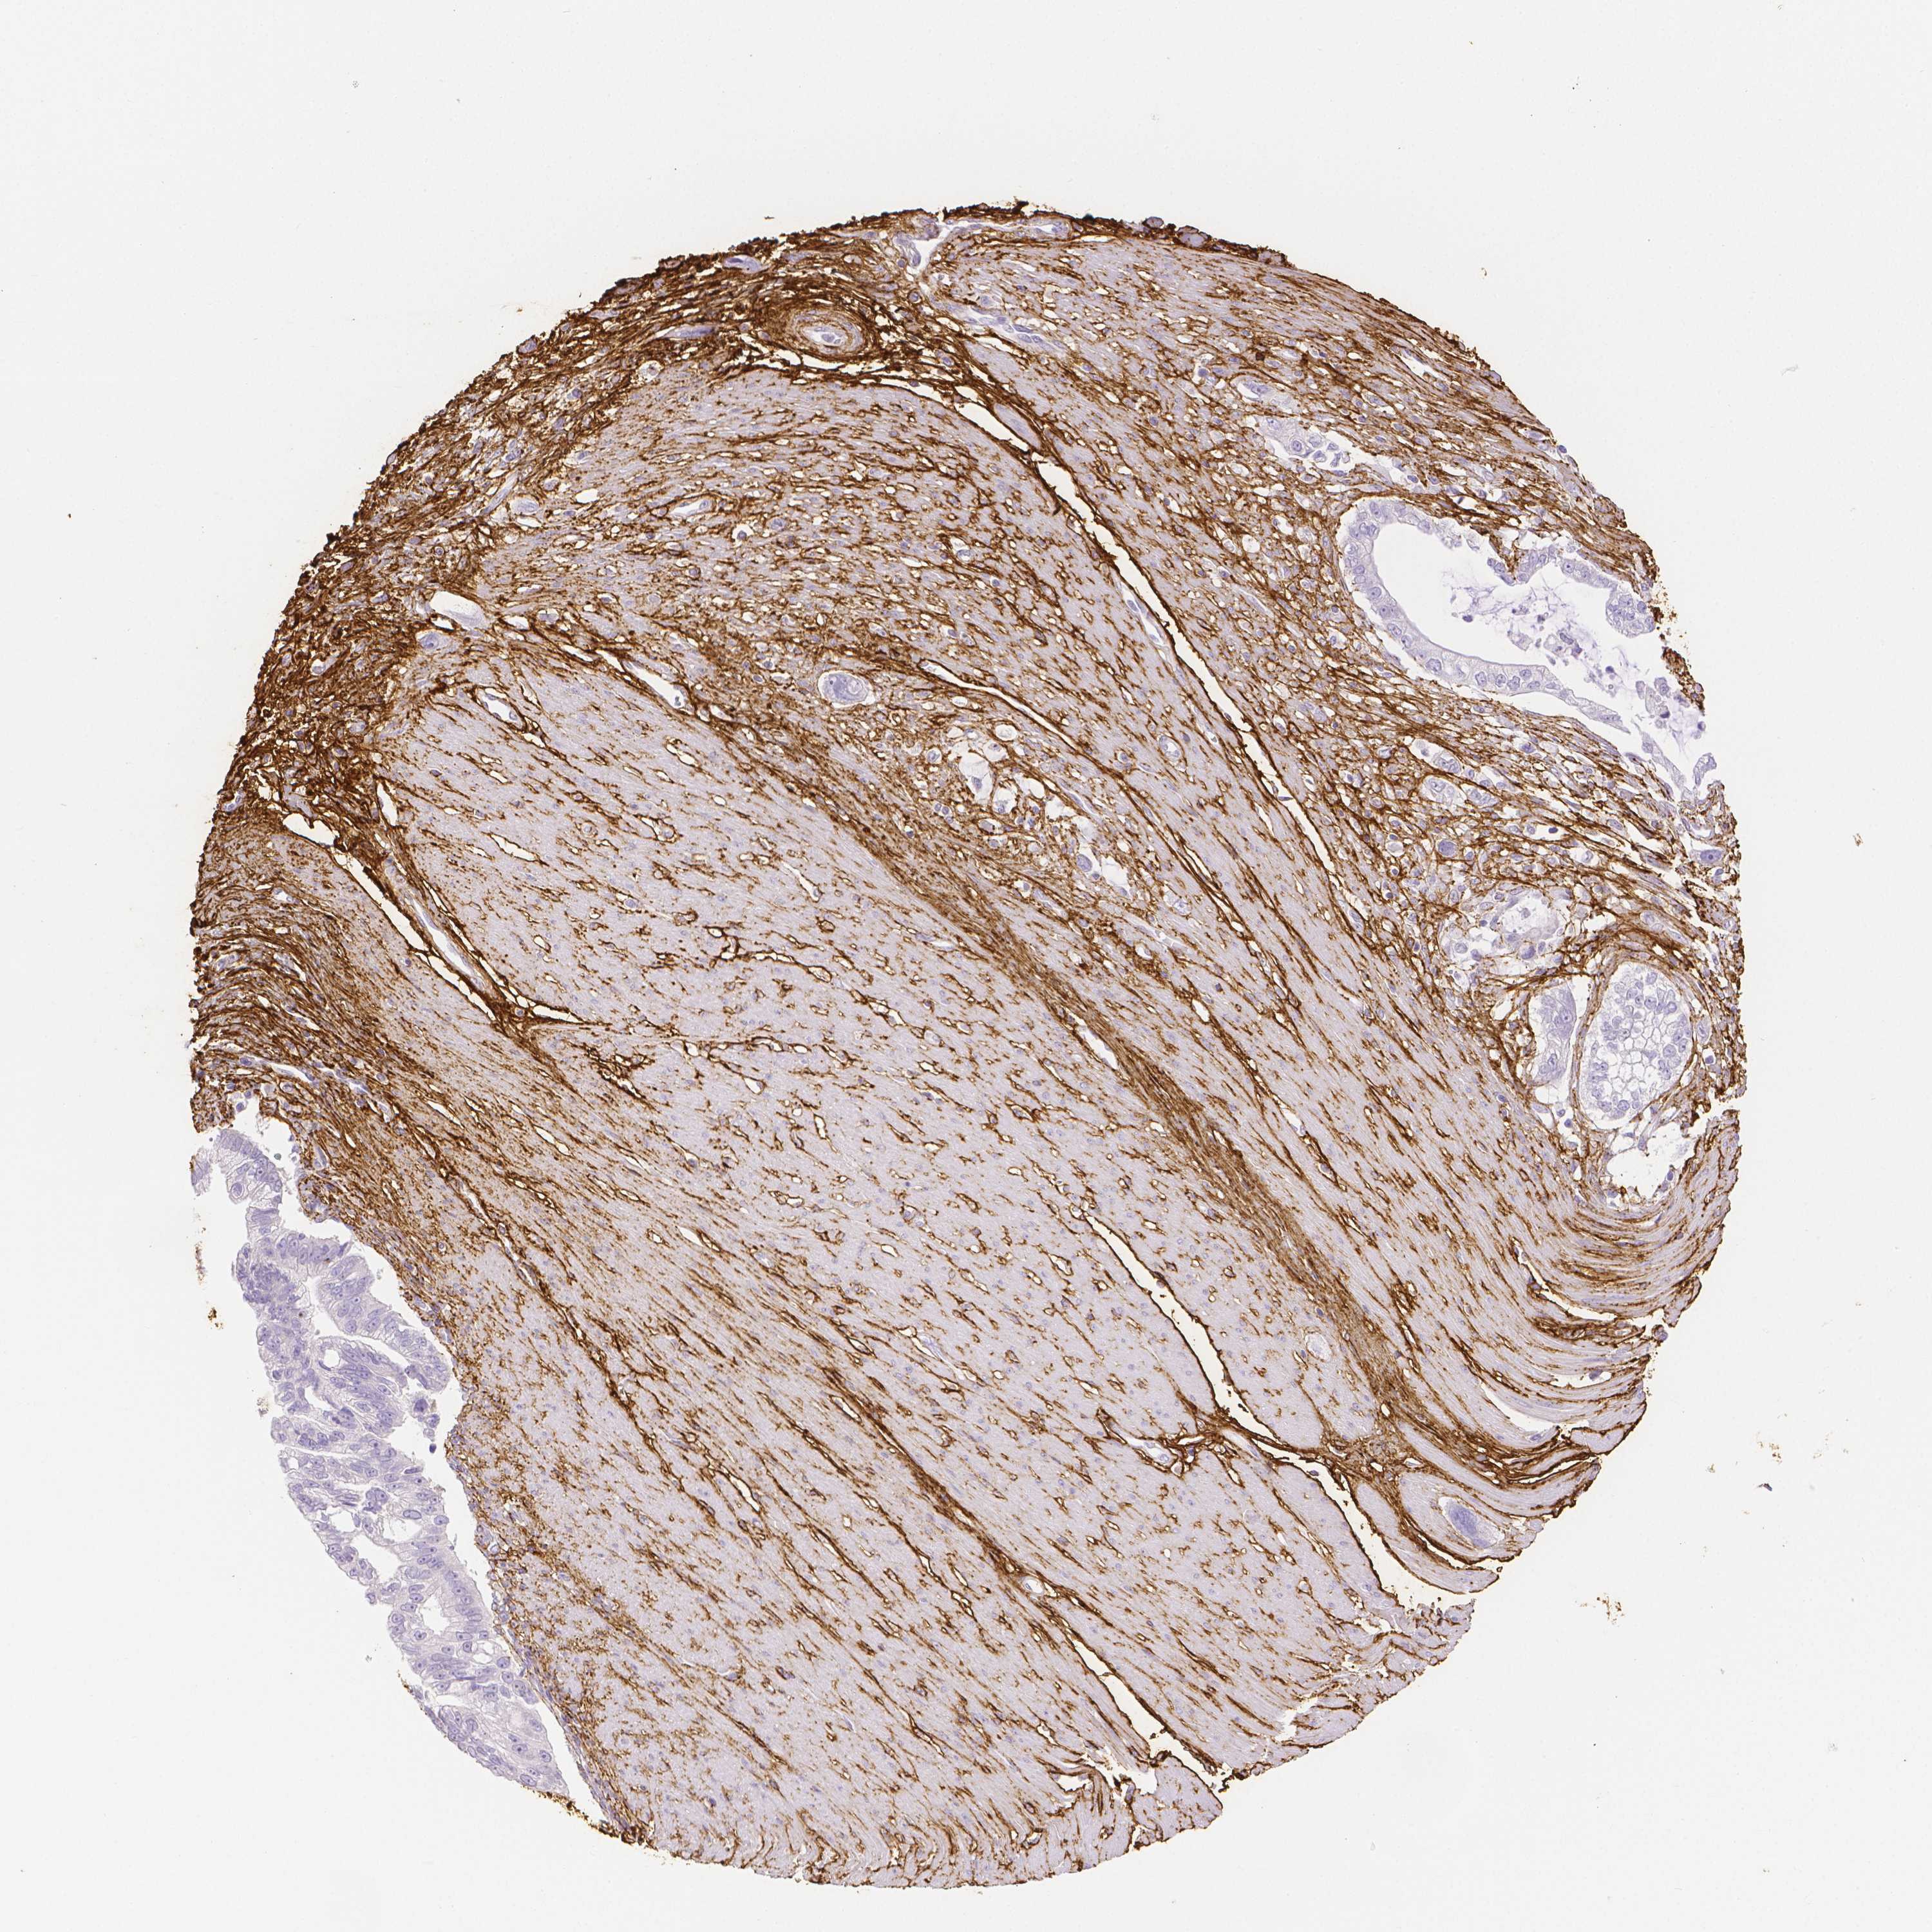

PANCREATIC CANCER - Protein expressioni

A mouse-over function shows sample information and annotation data. Click on an image to view it in a full screen mode. Samples can be filtered based on level of antibody staining by selecting one or several of the following categories: high, medium, low and not detected. The assay and annotation is described here.

Note that samples used for immunohistochemistry by the Human Protein Atlas do not correspond to samples in the TCGA dataset.

Antibody stainingi

Antibody staining in the annotated cell types in the current human tissue is reported as not detected, low, medium, or high, based on conventional immunohistochemistry profiling in selected tissues. This score is based on the combination of the staining intensity and fraction of stained cells.

Each image is clickable and will lead to virtual microscopy that enables deeper exploration of all samples and also displays staining intensity scores, fraction scores and subcellular localization as well as patient and tissue information for each sample.

HPA017759

HPA021057

CAB002670

CAB058696

CAB068188

CAB080202

Staining

High

Medium

Low

Not detected

Intensity

Strong

Moderate

Weak

Negative

Quantity

>75%

75%-25%

<25%

None

Location

Nuclear

Cytoplasmic/membranous

Cytoplasmic/membranous,nuclear

Adenocarcinoma, NOS

Adenocarcinoma, metastatic, NOS